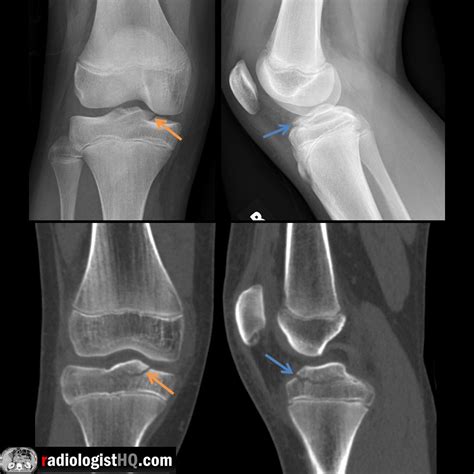

• Fractures: The epiphyseal plate is particularly vulnerable to injuries in children, as it is the weakest part of the growing bone. Fractures involving the epiphysis require careful management to ensure proper healing and to minimize the risk of growth disturbances. Pediatric nurses are involved in the initial assessment, stabilization, and ongoing care of these injuries.

• Initial Assessment: Conduct a thorough history and physical examination, focusing on the mechanism of injury, pain, swelling, and deformity. Assess neurovascular status to rule out any complications.

• Imaging Studies: Order appropriate imaging studies, such as X-rays, to visualize the epiphysis and identify any fractures or dislocations. In some cases, advanced imaging such as MRI may be necessary to assess soft tissue injuries.